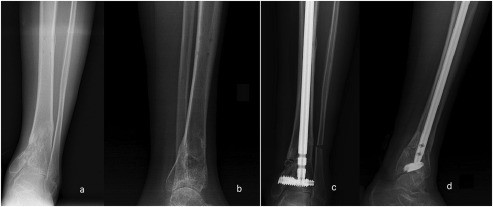

A 49-year-old man suffered a traffic accident. He had an AO type A2-3 fracture of the tibia with no additional injury. He had been operated in a different clinic with Kirschner wires. Three months after the first operation, revision was made with an Ilizarov external fixator and followed up for 7 months at the same clinic. The patient was admitted to our clinic with complaint of pain, inability to walk, and limited ankle movement. Anteroposterior (AP) and lateral ankle X-rays were obtained (Fig. 2 a and b). Malunion and severe complex regional pain syndrome with deformity were diagnosed.

Fig. 2.

Preoperative AP (a) and lateral (b) , and postoperative AP (c) and lateral (d) X-rays of Patient 1.

A varus producing close-up osteotomy was performed. A 40 × 8-mm DSBLS was inserted parallel and 4 mm above the ankle joint. Two osteotomies were constructed to produce a 12° wedge, which was then removed. The distal osteotomy was 22 mm proximal to the ankle joint. There was nonunion of the fibula at the level of center of rotation of angulation, so that osteotomy was not required for the fibula. Following removal of the wedge, the cut surfaces were opposed, and a 360 × 1-mm nail was inserted through the distal face and interlocked. After interlocking, alignment was reassessed by using the calcaneocrural angle under fluoroscopy. The correction was controlled with postoperative AP-lateral X-rays (Fig. 2 c and d).